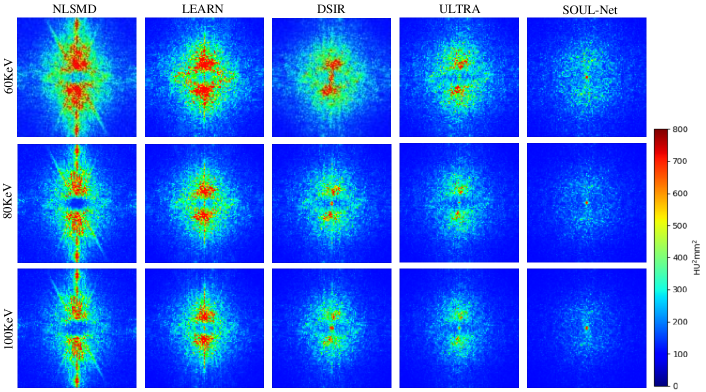

Figure 3: Absolute difference maps of abdominal images between different reconstruction results and references.

Refer to caption

Figure 4: NPS maps of abdominal images from different reconstruction results in 60, 80 and 100 KeV energy bins.

To better verify the detail recovery ability, Fig. 3 shows the absolute difference images associated with the reference image. In Fig. 3, it is clear that SOUL-Net has the smallest residual compared with other methods. This indicates that our method is able to preserve the structural details effectively.

The NPS of all results are shown in Fig. 4. We can see that in both high- and low-frequency bands, the error in the results of SOUL-Net is lower than that of the other methods. This can be treated as additional evidence of the effectiveness of our proposed method.